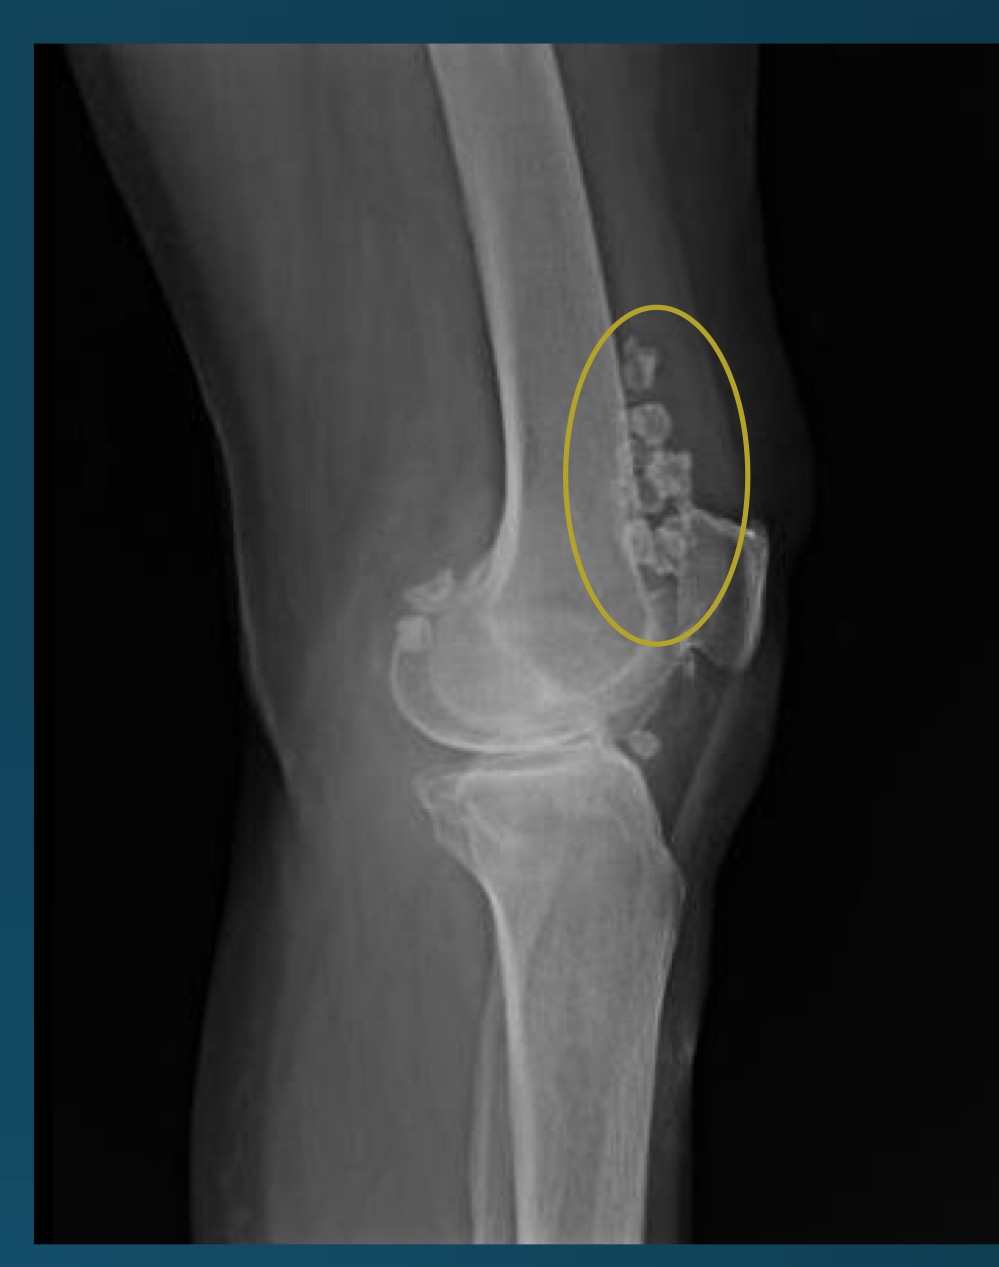

what is this finding?

synovial chondromatosis (SCM)

what is the most commong site for synovical chrondomatosis

knee

loose bodies from synovial chondromatosis might predispose the patient to?

degenerative osteoarthritis

what do you call this feature? what diagnosis is this part of ?

apple core deformity, synovial chondromatosis